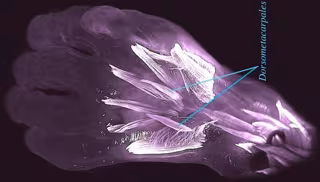

Dorsometacarpales en un embrión humano

Dorsometacarpales en un embrión humano - RUI DIOGO, NATALIA SIOMAVA Y YORICK GITTON

Sorprendentemente, algunos de estos músculos, como los dorsometacarpales que se muestran en la imagen, desaparecieron de nuestros antepasados adultos hace más de 250 millones de años, durante la transición de reptiles sinápsidos a mamíferos, según hallazgos revelados por nuevas tecnologías de imagen publicados en la revista Development.